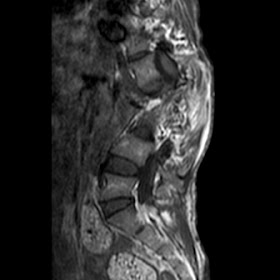

Radiological images (MRI):